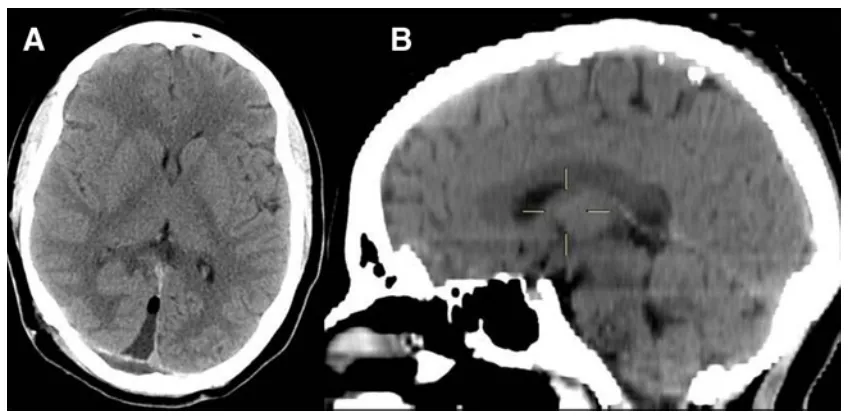

复查核磁共振时,医生的眉头微微皱起:“囊肿长到16毫米了(图2),虽然只大了3毫米,但结合症状加重,我建议手术。”

图2术前MRI,3年后复查,囊肿略增大(直径16 mm)。

术后过程平稳,豆豆仅出现了短暂的视力模煳,24小时内就自行恢复了。病理检查提示为松果体囊肿,周围包绕一层毛细胞样胶质层。术后6个月随访,豆豆头痛无复发,恢复良好。

图3术后即刻CT证实囊肿已完整切除。由于右枕叶牵拉,手术入路通道仍清晰可见(a)。